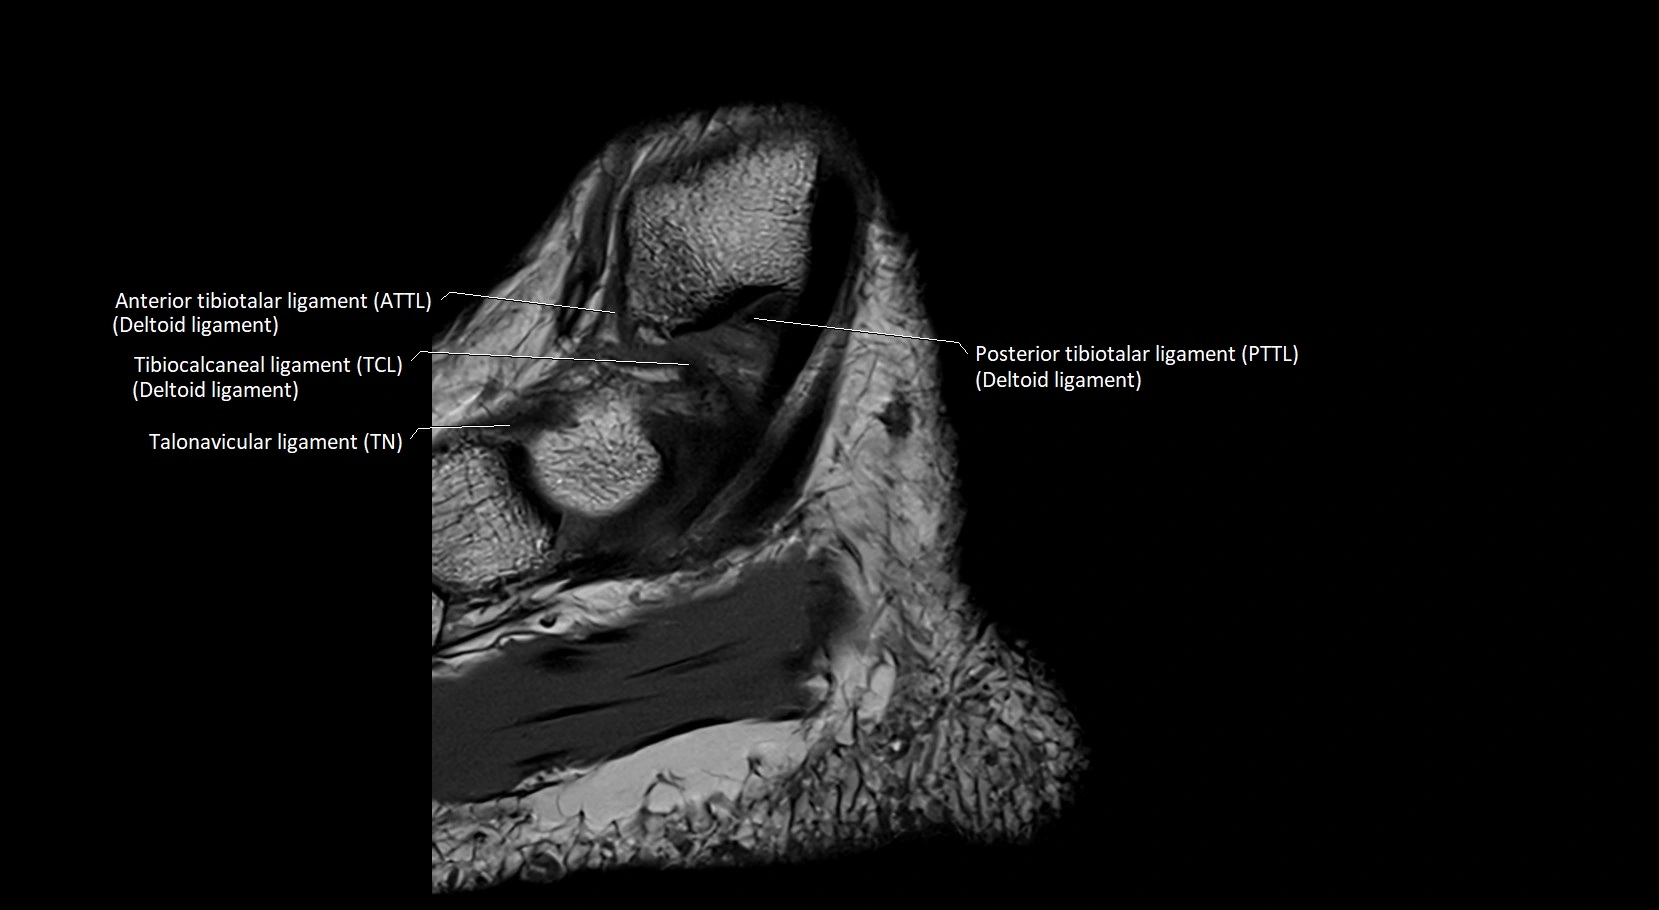

MRI image

image